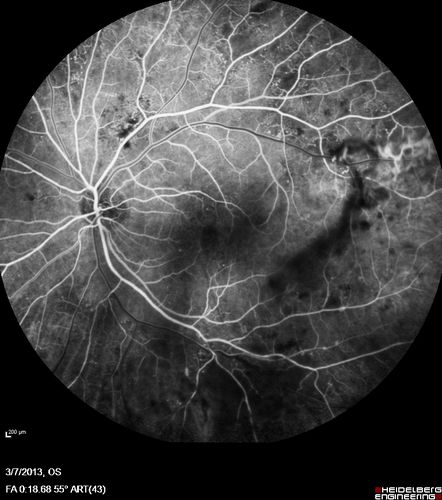

Proliferative Diabetic Retinopathy and Vitreous Hemorrhage - FA shows leakage of dye from NVE

NVE (neovascularization elsewhere) and Vitreous Hemorrhage